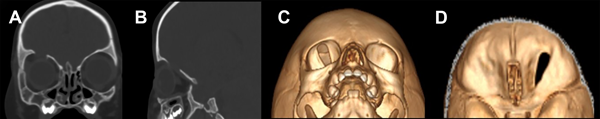

Paciente masculino de 2 años que ingresó a la guardia de nuestra institución por un TEC leve, secundario a una caída de altura. A su ingreso se constató una escala de Glasgow de 14/15, un cefalohematoma frontal y edema bipalpebral derecho. En la TC de ingreso se evidenció una fractura de cráneo lineal en el techo de órbita derecha sin otras lesiones asociadas (Figura 1).

Figura 1. TC de encéfalo. A) Ventana ósea corte coronal. B) Ventana ósea corte sagital. C y D) Reconstrucción 3D. Se observa fractura lineal de techo de órbita derecha (flecha amarilla).